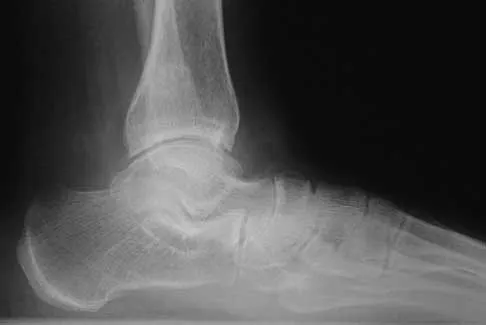

A previously asymptomatic 14-year-old girl sustained a twisting injury to her ankle. Radiographs are shown in Figures 2a and 2b. Management should consist of

The radiographs show a well-defined, irregular, eccentric lesion in the distal tibia metaphysis with a thin sclerotic margin. The radiographs are diagnostic of nonossifying fibroma, a common entity in this age group and in this location. No further work-up is indicated. The patient was asymptomatic prior to the injury and the lesion is small and thus not worrisome for an impending pathologic fracture; therefore, no treatment is indicated beyond observation. The natural history of these lesions is to gradually ossify as the patient reaches skeletal maturity. Menendez LR (ed): Orthopaedic Knowledge Update: Musculoskeletal Tumors. Rosemont, IL, American Academy of Orthopaedic Surgeons, 2002, pp 69-75.